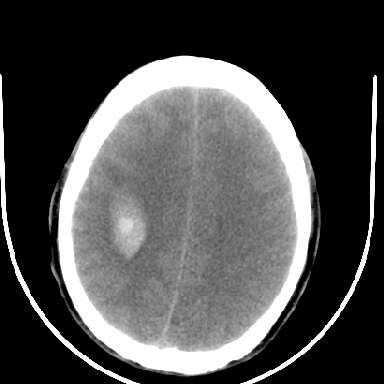

标题: CT6056:脑出血(血管畸形?) [打印本页]

标题: CT6056:脑出血(血管畸形?)

m 40突发头痛左侧偏瘫3小时

2增强时占位效应加重了,考虑出血还没有停止

但脑出血早期做增强是不是有点太冒险了?

术中抽出40ml陈旧血液,血肿底部似见一条索血管影